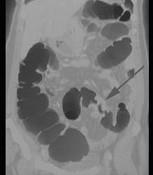

男,55岁,左下腹胀痛、并可触及包块,结合图像,应诊断为 ( )A.结肠Crohn病B.结肠癌C.结肠腺瘤D.肠结核E.慢性溃疡性结肠炎

问题 男,55岁,左下腹胀痛、并可触及包块,结合图像,应诊断为 ( )

选项 A.结肠Crohn病 B.结肠癌 C.结肠腺瘤 D.肠结核 E.慢性溃疡性结肠炎

答案 B